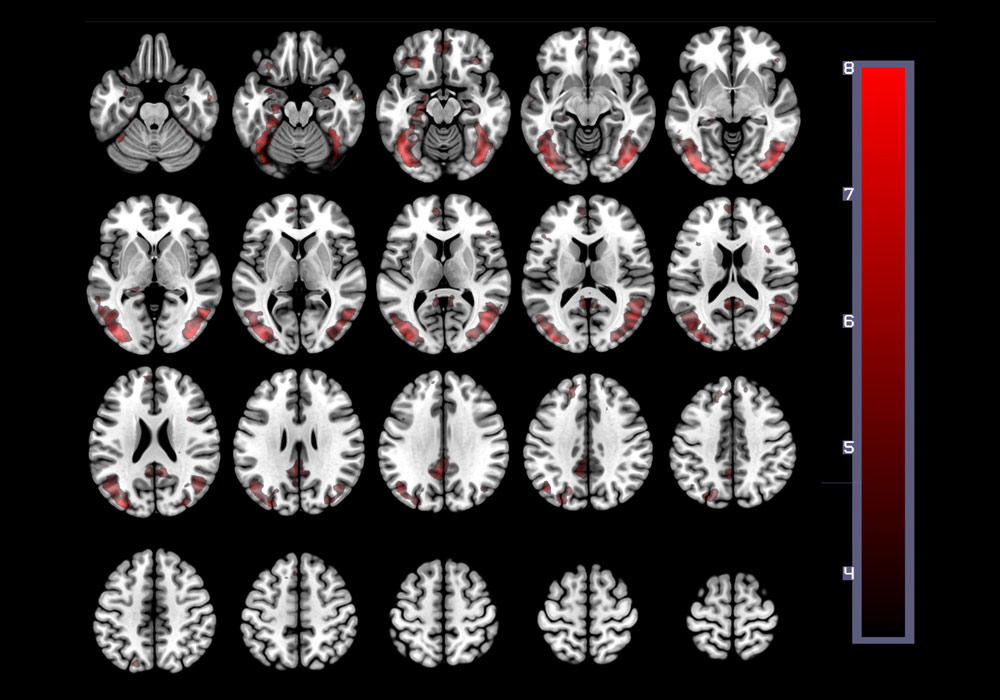

South Carolina awards more than 4,000 health care-related degrees annually to future clinicians, technicians, researchers and educators who believe in the transformative power of medicine. A state-of-the-art, 16-acre health sciences campus under development in Columbia promises cutting-edge diagnostics and treatment, with an emphasis on Alzheimer’s, stroke and other neurological conditions.